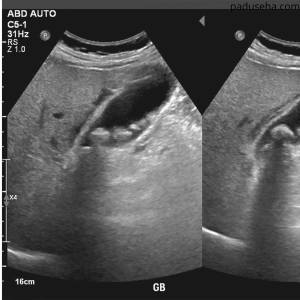

Berikut Adalah Terjadiinya Batu Empedu Akibat Ginjal Bermasalah